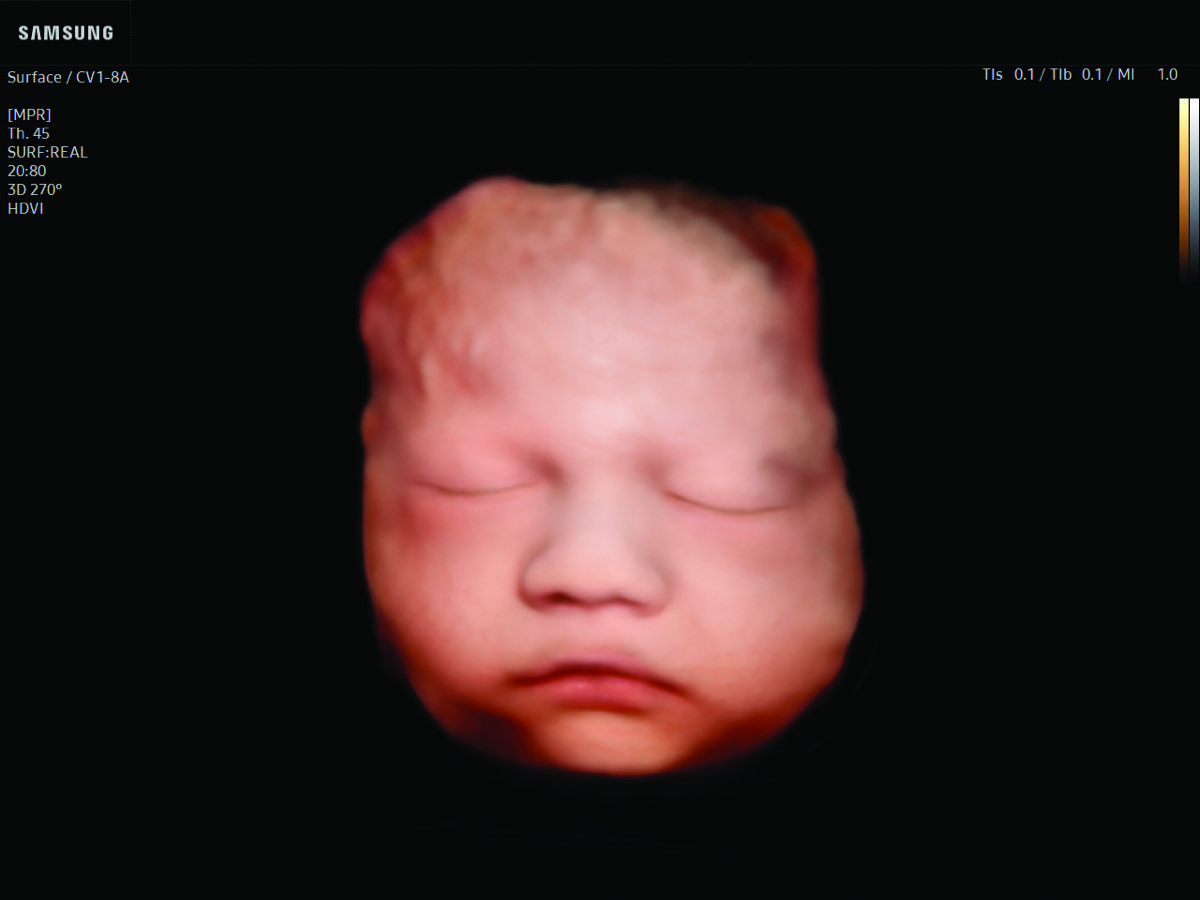

Comprehensive, advanced and expert MFM care for high-risk pregnancies

- Fetal anomalies